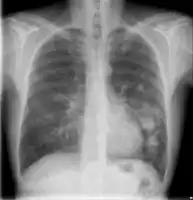

Chest X-ray of lungs affected by cryptococcosis